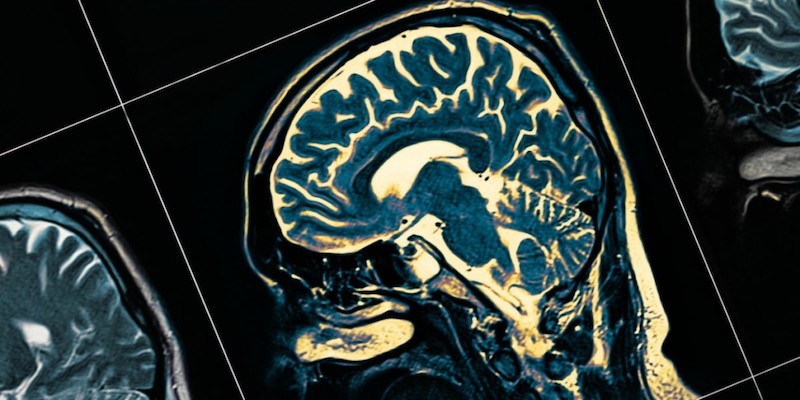

El Alzheimer, conocido por su difícil detección en fases iniciales, se caracteriza por la acumulación anormal de dos proteínas en el cerebro: la beta amiloide, que forma placas, y la tau, que se agrupa en ovillos neurofibrilares. Estos ovillos son un marcador distintivo de la enfermedad y están directamente relacionados con el deterioro cognitivo.

La nueva prueba, basada en el análisis de biomarcadores en el líquido cefalorraquídeo, detecta la formación de estos ovillos de tau hasta una década antes de que sean visibles en exploraciones cerebrales tradicionales, como la tomografía por emisión de positrones (PET).